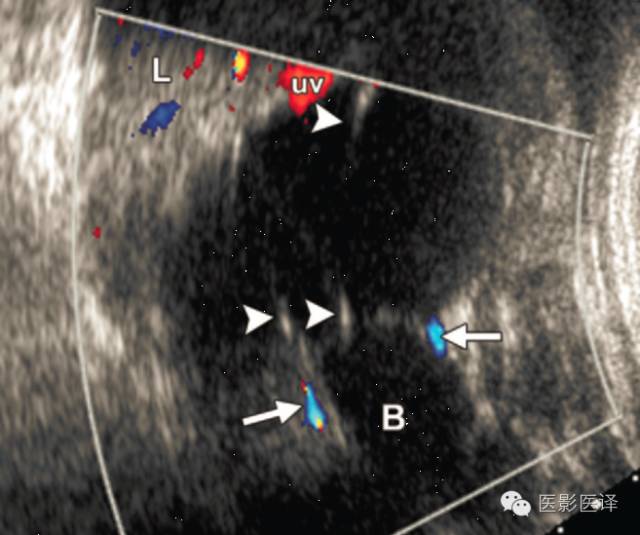

超声检查中,复杂性卵巢囊肿是厚壁的,且回声不均质。图像特征包括多个分隔(图4、5)、内部移动性高回声、实性表现(图6),或液液平面(图5、7)。复杂性囊肿被认为是扭转的结果,胎儿比新生儿更常发生。出现复杂性囊肿的表现高度提示需要手术。与胎儿卵巢囊肿伴发的其他影像表现包括羊水过多和腹水,可能是由于漏出或囊肿破裂所致。肠管或肾脏的继发梗阻被认为是扭转时卵巢坏死引起的粘连所致。

图4.多分隔卵巢囊肿。冠状位超声多普勒图像显示一个分界清楚的腹内囊肿,位于膀胱(B)上方及肝脏(L)下方,分隔较薄且壁无血管(箭头),双侧脐动脉(箭)是分辨胎儿膀胱的解剖标记。脐静脉(uv)在囊肿上缘上方进入肝内。